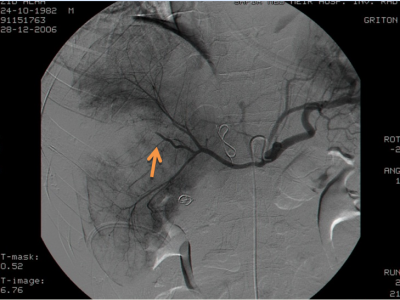

- אנגיוגרפיה בררנית (סלקטיבית) של עורק הכבד, העורק המזנטרי העליון ועורק הטחול נותנת מידע ישיר על מקום הקרע וגודלו (תצלום 11.10).

אי-ספיקת כבד - אי-ספיקת כבד לאחר חבלה היא נדירה ומופיעה כסיבוך של מחלות זיהומיות אחרות. המוביליה חבלתית - בחבלה חודרת עמוקה של הכבד, כאשר לא קושרים את כלי הדם והמרה, נוצר במשך הזמן קשר בין כלי הדם והמרה וכלי המרה מתחילים להתמלא בדם ובקרישים. התמונה הקלינית אינה מופיעה מיד אלא 3-4 שבועות לאחר החבלה ומתבטאת בכאבים עוויתיים, בצהבת קלה ובצואה שחורה (מלנה) או בהקאת דם (המטמזיס). במעבדה ניתן למצוא עלייה ברמת הבילירובין, עלייה ברמת הפוספטאזה הבסיסית ועלייה בריכוז האספרטאט טרנסאמינאזה. האבחנה נקבעת בעיקר על-ידי ארטריוגרפיה דרך עורק הכבד, אולם גם בדיקות כמו כולאנגיוגרפיה או ספלנופורטוגרפיה יכולות לעזור. הטיפול כרוך בכריתה מחדש של האזור שנפגע וקשירה קפדנית של כלי הדם והמרה. ביצוע של כולאנגיוגרפיה וארטריוגרפיה תוך-ניתוחית עוזרים בקביעת מיקום הפגיעה. פרטים אודות הטיפול ראה בסעיף על המוביליה.